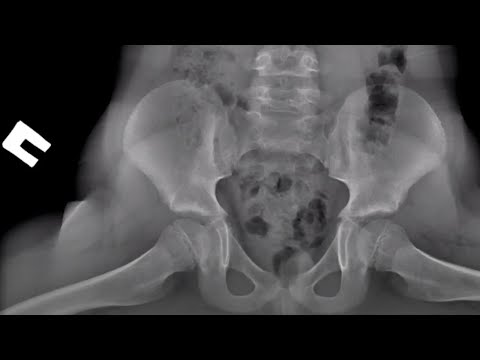

Укладка для КТ органов брюшной полости с контрастным усилением